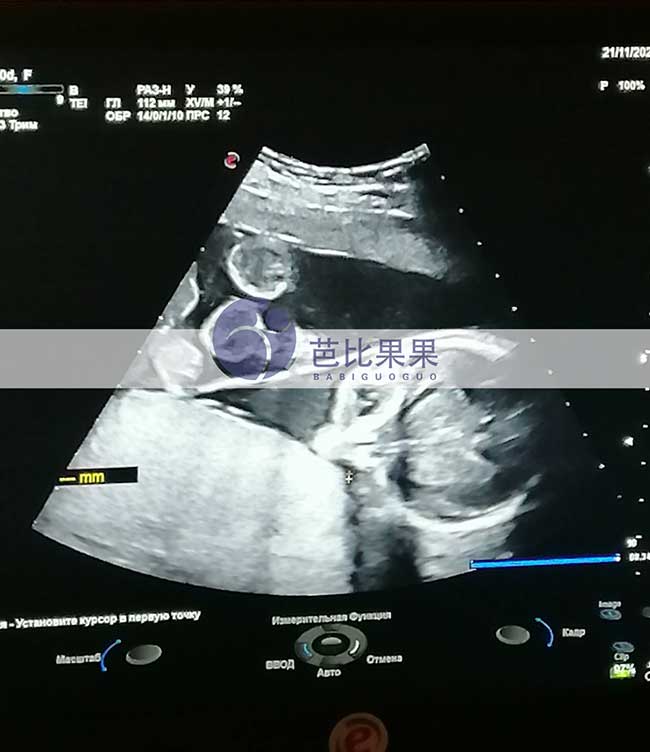

J先生的乌克兰试管妈妈按时基辅妇产医院做孕17周B超孕检

J先生家乌克兰试管妈妈按时到我们熟悉的基辅妇产医院做孕17周B超孕检,胎儿发育得很好,孕妈身体状态也很好,辛苦她了